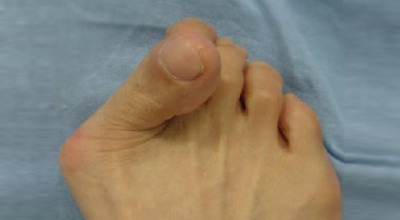

무지외반증이 심해지면 엄지발가락이 두 번째 발가락과 겹치거나 관절이 탈구되어 전반적으로 발을 디디기 어려운 상태가 될 수 있습니다. 건강보험심사평가원의 무지외반증 환자 통계에 따르면, 40대 이상에서 가장 많이 발생하며, 여성 환자 비율이 남성보다 월등히 높다고 합니다.

육안으로 확연히 엄지발가락의 변형이 보이며, 초기에는 굳은살이 생기고 약간의 통증도 동반됩니다. 엄지발가락의 돌출 부위에 통증이 발생하는데, 이 부위가 신발에 자극을 받아 두꺼워지고 염증이 생겨 통증이 유발됩니다. 발바닥에 굳은살이 생기면 정상적인 보행이 어려워지고, 심한 경우에는 통증 때문에 신발 착용이나 정상적인 보행도 힘들어질 수 있습니다. 증상이 지속적으로 악화되면 엄지발가락이 겹치거나 탈구될 수도 있습니다.